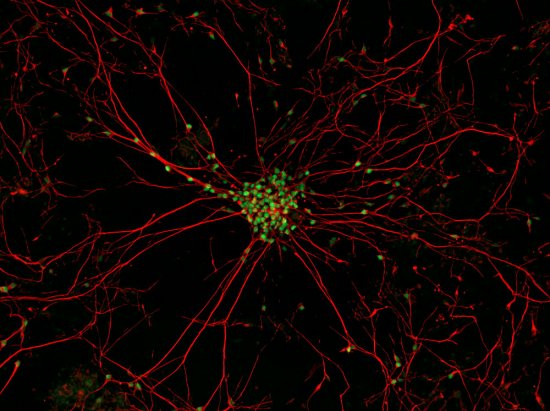

10.肌萎缩侧索硬化症患者皮肤细胞

肌萎缩侧索硬化症患者皮肤细胞

经过特殊处理,肌萎缩侧索硬化症患者的皮肤细胞变成了干细胞,接着干细胞又分化为运动神经元,即引发这种疾病的细胞。美国哥伦比亚大学的吉斯特·克罗夫特和肌萎缩侧索硬化症医疗计划的马肯兹·威甘特(Mackenzie Weygandt)利用反向荧光显微镜拍下了运动神经元宽25微米的细胞核(绿色)及其长长的连接纤维(即轴突,红色),以便用健康细胞同病变细胞进行比较。